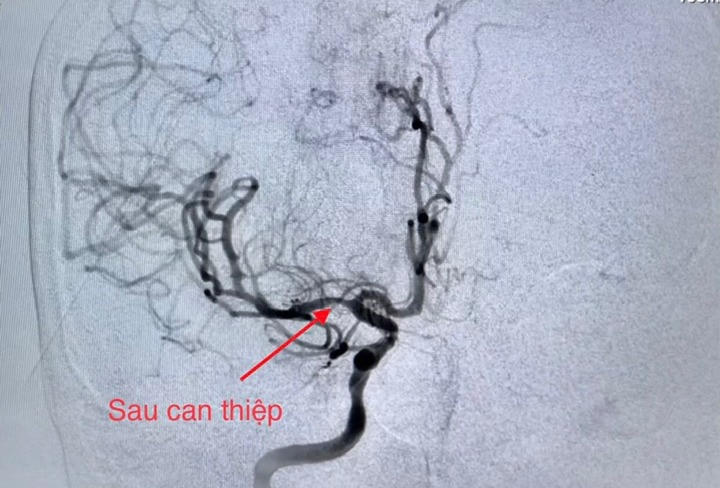

Ê-kíp can thiệp tim mạch trong thời gian khoảng 40 phút đã hoàn tất nong động mạch vành bị tắc và tiến hành đặt giá đỡ (stent), giúp tái lập dòng máu nuôi tim. Ngay sau đó ê-kíp can thiệp mạch não chụp kiểm tra phát hiện tắc động mạch não giữa bên phải; thủ thuật lấy huyết khối tái thông mạch máu bị tắc với thời gian 20 phút.

Hình DSA mạch não sau can thiệp |

Kết quả chụp cộng hưởng từ kiểm tra ngày hôm sau cho thấy mạch máu não bị tắc đã tái thông tốt. Hiện tại, bệnh nhân đã tỉnh, sinh hiệu ổn định, không còn đau ngực, không rối loạn ngôn ngữ, còn yếu nhẹ nửa người bên trái.